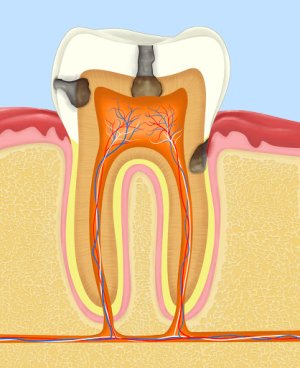

Артерии, отвечающие за кровоснабжение зубов

- Верхнечелюстная артерия. Крупная конечная ветвь наружной сонной артерии. С топографической точки зрения имеет три части: нижнечелюстную, крыловидную и крыловидно-небную.

- Нижний альвеолярный артериальный сосуд. Проходит между медиальной крыловидной мышцей и веткой нижней челюсти, доходит до подбородочного отверстия.

- Зубные ветви. Направляются к корням зубов.

- Жевательный артериальный сосуд. Небольшого размера, проходит над вырезкой нижней челюсти и снабжает кровью жевательную мышцу.

- Челюстно-подъязычная ветка. Начинается с отверстия нижней челюсти и совместно с челюстно-подъязычной мышцей пролегает в одноименной борозде.

- Щечный артериальный сосуд. Снабжает кровью десны и щеки, находится в щечной мышце.

- Задняя верхняя альвеолярная артерия. Заходит ответвлениями в альвеолярные каналы, кровоснабжает верхние моляры, десны и слизистую поверхность верхнечелюстной пазухи.